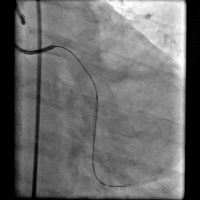

冠脉造影

造影时间: 入院当天03:35~03:52。

造影结果(一): 前降支近段闭塞,回旋支中远段90%狭窄。

造影结果(二): 右冠中段闭塞。

造影结论及应对策略: 前降支近段闭塞,回旋支中远段90%狭窄,右冠中段闭塞,未行左室造影。病变血管:前降支;回旋支;右冠。与家属沟通,同意行PCI。